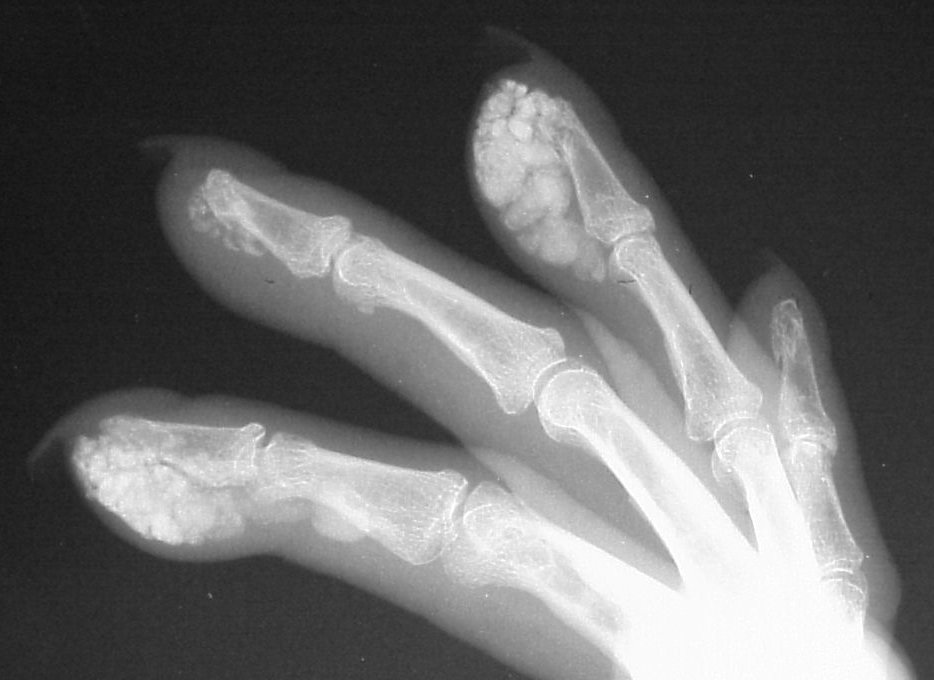

Clinical Example: CREST syndrome with scleroderma, telangiectasias and subcutaneous calcification

Scleroderma is a systemic disease, but commonly affects the hands in several ways. Finger stiffness is typical. Scleroderma may be associated with other syndromes, and a common combination is Calcinosis, Raynaud's, Esophageal motility disorders, Scleroderma and Telangiectasias - CREST syndrome. In this syndrome, the hands are affected by calcinosis, Raynaud's and scleroderma. Skin ulcerations may arise from Raynaud's related peripheral vascular insufficiency (fingertips), from scleroderma related skin tightness (extensor surfaces of the proximal interphalangeal or metacarpophalangeal joints), or from extrusion of subcutaneous calcium formations (any location).

Xrays show extensive soft tissue calcifications of the distal pulp of these fingers.

Soft tissue calcifications are typically diffuse, and can not be simply "shelled out". Thorough excision may lead to extensive skin loss, and partial removal (limited incision and drainage) may be a reasonable compromise approach in selected cases.